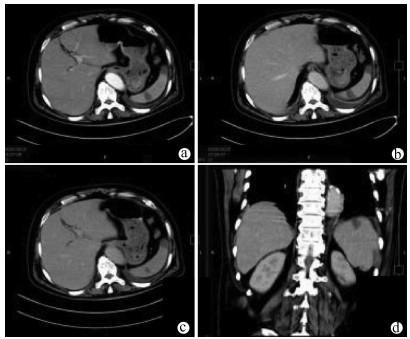

Value of SpyGlass single-operator choledochoscopy system in the diagnosis and treatment of patients with biliary tract diseases

Si ZHAO, Xueru WU, Linlin YIN, Lin MIAO, Guozhong JI, Xiuhua ZHANG

2021, 37(10): 2395-2399. DOI: 10.3969/j.issn.1001-5256.2021.10.027

Abstract(2477) HTML (634) PDF (2327KB)(122)

Abstract:

Objective  To investigate the value of SpyGlass single-operator choledochoscopy system in the diagnosis and treatment of patients with unexplained biliary stricture, complex bile duct stones, or other biliary tract diseases.  Methods  A retrospective analysis was performed for the clinical data of the patients with biliary tract diseases who were diagnosed and treated with SpyGlass in The Second Affiliated Hospital of Nanjing Medical University from December 2017 to June 2020. For the patients with biliary stricture, the biliary lesions were fully visualized under the guidance of SpyGlass, and SpyBite biopsy was performed if necessary; the patients with bile duct stones were treated with SpyGlass-guided direct-view laser lithotripsy; for the patients with gallbladder disease, the cystic duct was superselected with the assistance of SpyGlass. The SpyGlass system was analyzed in terms of its sensitivity, specificity, and accuracy rate in diagnosis and treatment, lithotripsy success rate, stone clearance rate, procedure success rate, and incidence rate of complications.  Results  A total of 58 patients underwent SpyGlass procedure. SpyGlass was used to evaluate biliary stricture of unknown nature in 44 (76%) patients; SpyGlass visual impression had a diagnostic sensitivity of 92% (24/26), a specificity of 94% (17/18), and an accuracy of 93% (41/44), and SpyBite biopsy had a diagnostic sensitivity of 71% (15/21), a specificity of 92% (11/12), and an accuracy of 79% (26/33). SpyGlass was used for the treatment of bile duct stones in 8 patients (14%), with a lithotripsy success rate of 83% (5/6) and a stone clearance rate of 88% (7/8). A guide wire under the SpyGlass system was to superselect the cystic duct in 5 patients (9%), with a procedure success rate of 80% (4/5). In one patient (1%), SpyGlass was used to assist the removal of common bile duct stones after liver transplantation and the treatment of bile duct anastomotic stricture. A total of 5 patients (9%) experienced complications after surgery.  Conclusion  The SpyGlass choledochoscopy system is accurate, safe, and effective in the diagnosis and treatment of unexplained biliary stricture, complex bile duct stones, and other biliary tract diseases.